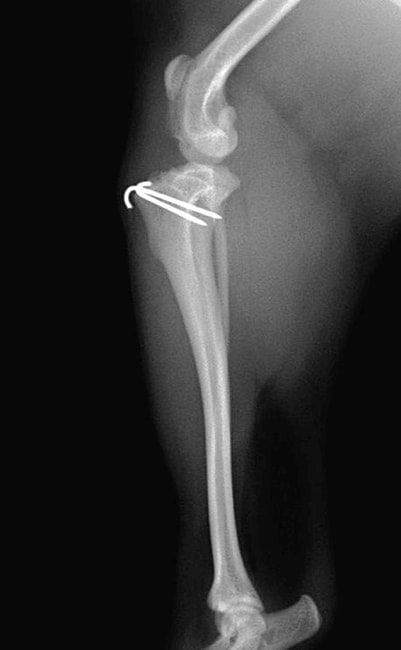

■ 症例24 キャバリア 7か月

左右膝蓋骨内方脱臼(左:グレードⅣ 右:グレードⅢ)

以前から左右後肢の跛行が認められ、整形外科学的検査・レントゲン検査により左右の膝蓋骨脱臼が認められた。症状が重度である左膝の膝蓋骨脱臼整復術を行った。外科手技は縫工筋及び内側広筋の解放、脛骨粗面の外側転位、滑車ブロック形造溝術、内外側関節方の縫縮を実施した。術後一か月時点で、左の膝蓋骨は安定しており経過は良好である。

本症例は成長期における重度の膝蓋骨脱臼であり、術後の再発の可能性もあるため、経過をしっかりと観察していく必要がある。また、今回手術を実施していない右膝に関しても経過を観察し、手術を検討していくこととする。